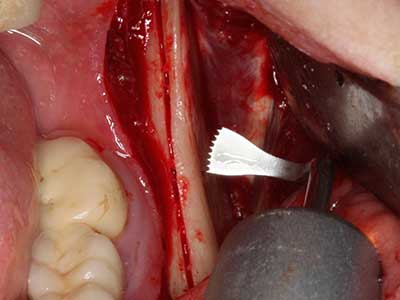

Piezo surgery has additional advantages when harvesting bone blocks. In addition to the high precision with osteotomy described above, the use of the thin saw tips specifically minimizes loss of material. Greater loss of material during harvesting can be expected with the thicker instrument tips, particularly when using Lindemann drills (Lakshmiganthan, Gokulanathan et al. 2012). The basal separation, which is necessary particularly for retromolar block transplants, is simplified by specially designed rectangular saws, with the result that piezo surgery is viewed as a precise, simple and safe procedure for harvesting retromolar bone blocks (Happe 2007) (Fig. 1-12).

Fig. 1: Preparation of a bone cover with the Piezomed (W&H Salzburg, Austria).

Fig. 3: Basal separation of the block is easier with specially angled attachments.